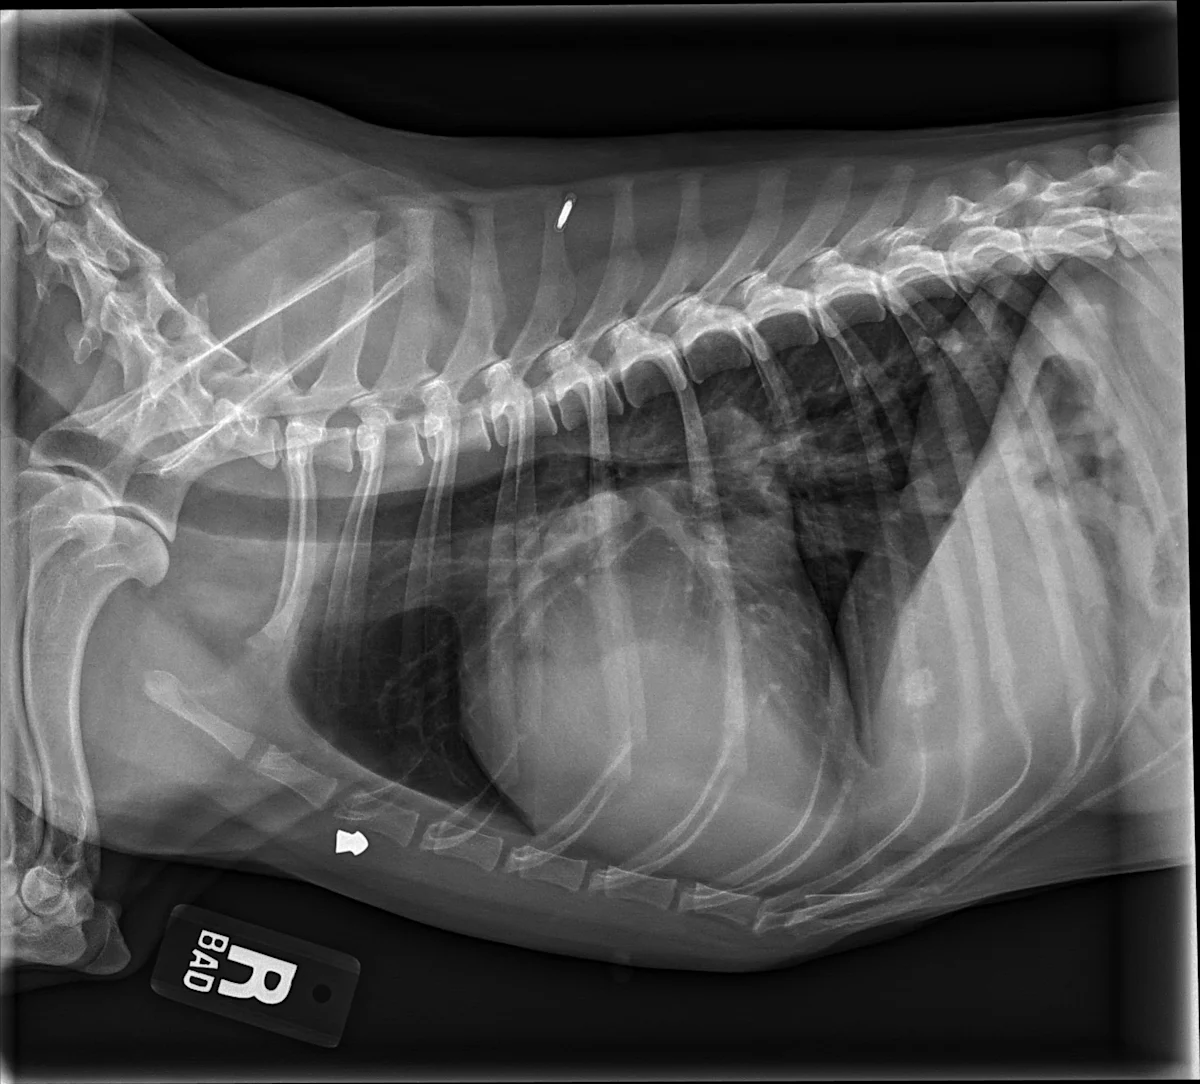

FIGURE 6 Right lateral and DV projections of 2 dogs with significant left-sided volume overload and heart enlargement secondary to MMVD. Moderate (A, B) and severe (C, D) changes can be seen. Dorsal elevation of the caudal portion of the trachea and mainstem bronchi secondary to heart enlargement, soft tissue opacity bulge in the region of the caudal waist representing the enlarged left atrium, and increased apicobasal length of the cardiac silhouette can be appreciated in the lateral views (B, D). Changes in the appearance of the borders of the left atrium and mainstem bronchi, as well as a visible auricular bulge in the DV view can be compared with those from a normal dog (Figures 1-3). An air gun ballistic (A, B) was also found incidentally. VHS, VLAS, M-VLAS, and VRHi collected from lateral view B are 11.4, 2.5, 4, and 3.6, respectively, and 12.7, 3.4, 5.9, and 4.1, respectively, collected from lateral view D.